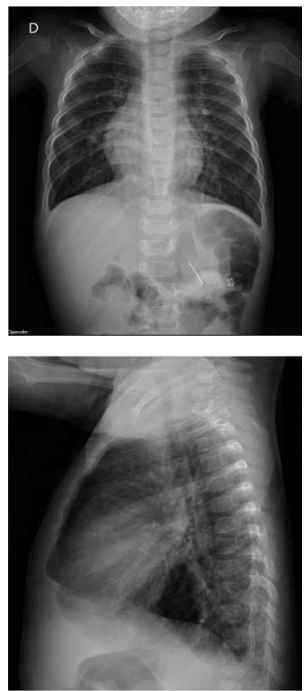

A radiografia de tórax e o eletrocardiograma, a seguir, de um lactente de 9 meses referem-se a qual cardiopatia congênita?

(Arquivo pessoal; imagens usadas com autorização)

Anomalia de Ebstein grave.

Atresia pulmonar com septo interventricular íntegro.

Transposição de grandes artérias clássica.

Defeito do septo atrioventricular total.

Drenagem anômala total de veias pulmonares supradiafragmática obstrutiva.